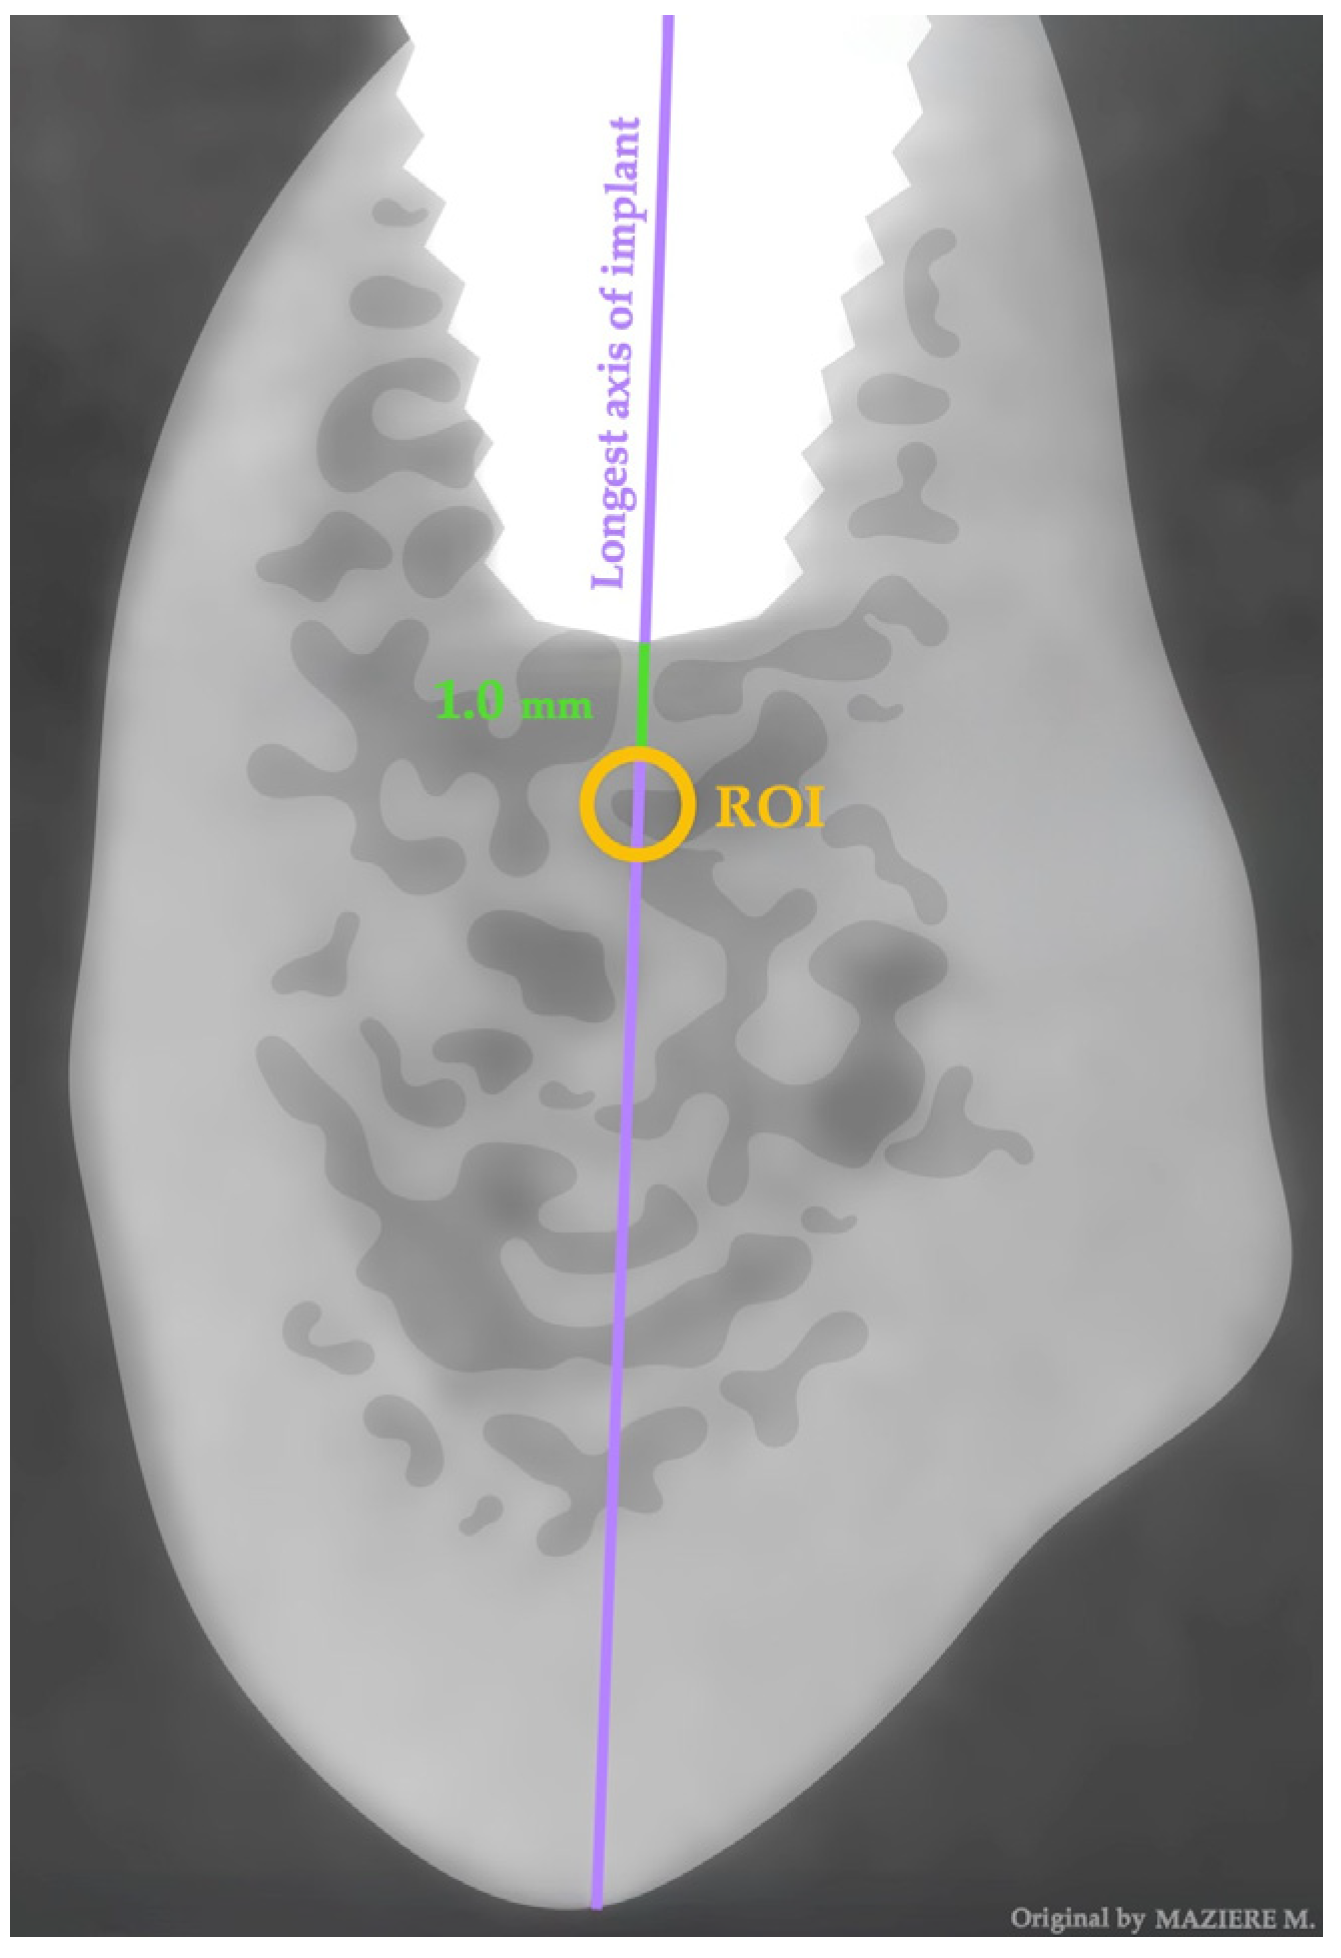

2.4. Data Extration—One Year Later